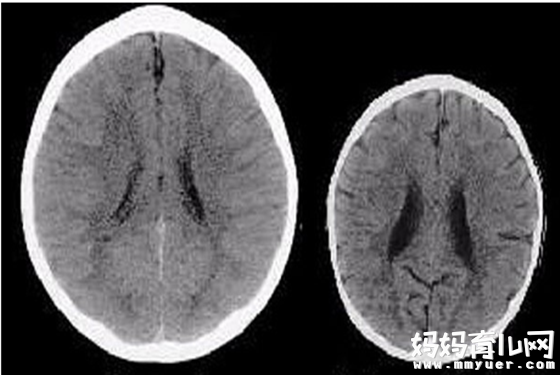

下面是两个三岁孩子的大脑扫描图,仔细看看它们有何不同?很明显,左边那个要比右边的大得多吧,同时,左边的大脑图片中“模糊”的黑暗区域更少。

那么,是什么导致二者大脑发生了如此巨大的差距呢?右边的孩子在发育过程中,到底发生了什么疾病或者可怕的事故?答案是NO~其实真正的原因是,两个孩子的母亲对待他们的方式。左边的孩子有一位很疼爱她的妈妈,对她的任何言行都予以温柔回应。而右边的孩子则经常被自己的母亲忽视和虐待。

神经学家解释称,右边的大脑容量明显少了很大一块,这缺失的区域会使得孩子不可能拥有一些能力。与左边的孩子相比,右边的孩子在成年时将没那么聪明,缺乏同情心,更有可能沉迷于毒品和参与暴力犯罪。同时,右边的孩子长大后也更容易事业,并面临精神疾病和其他严重的健康问题。